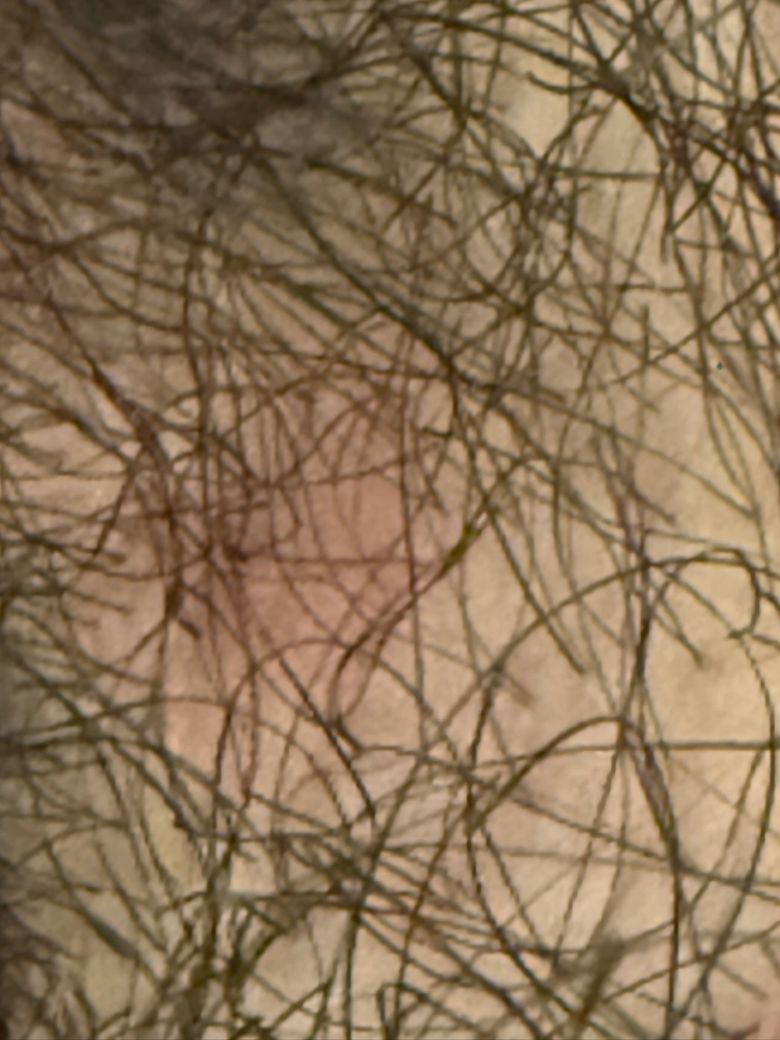

이게 낭종인지 단순한 종기인지 모르겠지만… 성기 바로 밑에(털난 부분)에 튀어나와있어서 물어봅니다.

먼저 이게 낭종이 맞는지 궁금합니다.

만약에 낭종이 맞다면 고약을 붙이는걸로 해결할 수 있는지 궁금합니다.

• 1번 째 사진

피지낭종, 모낭염 모두 감별해보아야 할것 같아요.

일반적으로 피지낭종이라 할지라도 고약을 붙이는 것은 근본적인 치료가 아니며, 보통은 외과적 절제나 , 배농을 하게 되지요. 보다 적절한 평가 시행 위해 비뇨의학과 또는 피부과 내원하여 진료 봐보실것 권유드립니다. 감사합니다.